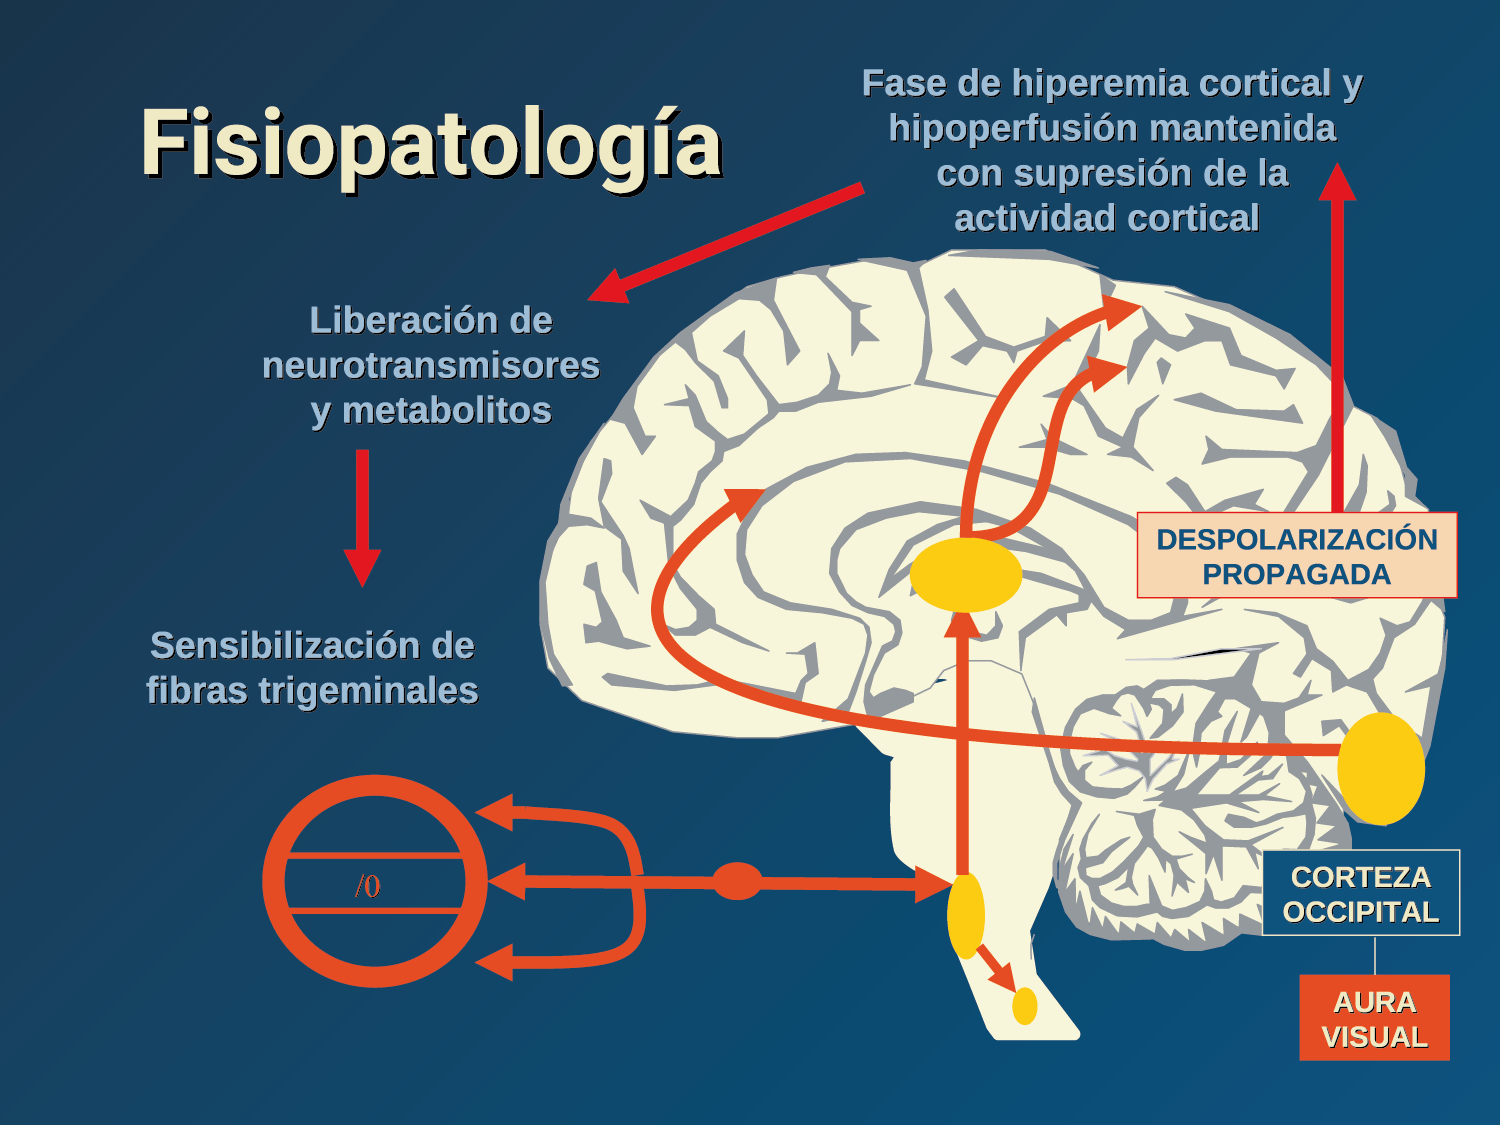

El aura de la migraña, al menos en su sentido clásico, tiene relación con la depresión cortical que se propaga por la corteza cerebral y participa como un actor paralelo cuando se producen las crisis. (Figura 2)

En la primera fase (figura 3), premonitoria, que precede a la cefalea, los sistemas del tronco encefálico y diencefálico modulan las señales aferentes, la fotofobia a la luz o la fonofobia al sonido, comienzan a disfuncionalizarse y eventualmente a evolucionar a la fase de dolor y con el tiempo a la fase de resolución o posdrómica. Aproximadamente en un tercio de los pacientes con migraña, sus ataques están asociados con déficits neurológicos, que incluyen perturbaciones corticales, denominadas colectivamente aura de migraña(3).

Ha existido una fuerte creencia de que la CSD, el correlato experimental del aura, es el principal evento desencadenante de la activación meníngea (la evidencia a favor y en contra se discutió anteriormente). Como se mencionó, el aura solo está presente en aproximadamente un tercio de los migrañosos, aunque es un sello común en las formas raras identificadas genéticamente. Hay pruebas contradictorias de excitabilidad cortical en la migraña; por un lado, las personas con migraña son más susceptibles a la activación visual y tienen una mayor sensibilidad a tales estímulos. Esto puede resultar de hiperexcitabilidad, particularmente en migraña con aura(99), con un umbral reducido para producir fosfenos(100). Sin embargo, existen informes similares de estados de hipoexcitabilidad y umbrales de fosfeno significativamente más altos(101). Parecería más razonable suponer que existe un cambio cortical alterado entre estados hipo e hiperexcitables que da como resultado una desregulación de la función cortical normal. Alternativamente, gran parte de la evidencia que respalda la hiperexcitabilidad puede resultar de alteraciones trigeminovasculares de orden inferior a través de las redes talamocorticales, como la participación talámica recientemente identificada en la fotofobia. (Figura 6)

Se cree que una onda transitoria de despolarización neuronal de la corteza (Figura 9), la depresión de propagación cortical (CSD), es el mecanismo cerebral fisiopatológico subyacente al fenómeno clínico del aura de la migraña. Leão(21) estableció un mecanismo subyacente hipotético. Luego de haber estimulado eléctricamente la corteza de conejo y encontrar una depresión EEG que se propagaba a una velocidad similar de 3 mm/min centrífugamente desde el sitio de estimulación sugirió que podría ser la base del aura migrañosa. Esta hipótesis está fundamentada en la correlación entre las características neurofisiológicas de una CSD, su propagación retinotópica en la corteza visual y las características y dinámicas de los déficits visuales(14, 15) y en las observaciones indirectas derivadas de los estudios de imágenes que respaldan aún más este concepto(16) Sin embargo, sobre la base de la comprensión actual de la migraña, es poco probable que la CSD esté involucrada en el inicio del síndrome completo de la migraña(17).